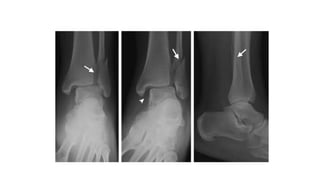

Đọc XQuang

AP

•Tibiofibular clear space : >5mm là bất

thường--> gợi ý tổn thương syndesmosis

•Tibiofibular overlap : <10mm là bất thường-

-> gợi ý tổn thương syndesmosis

•Talar tilt : > 2mm được xem như bất thường

Lateral view

• Gãy mắt cá sau

• Xương sên bán trật ra trước hoặc sau so với xương chày

• Di lệch và chồng ngắn của xương mác

• Các tổn thương phối hợp nếu có

Mortise view

• Các bất thường cần tìm kiếm:

• Medial joint space widening >

4mm --> gợi ý tổn thương dây

chằng denta

• Talocural angle <8 or > 15 độ ( khi

so sánh với chân đối diện)

• Ti/Fi overlap <1 mm